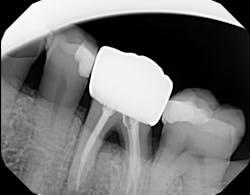

Technology solution: Many dental lasers can focus their beam smaller than 1 mm to enter the furcation for detoxification.8 For example, a 9.3-micron CO2 laser has a spot size of the focal laser beam in the control range of .25 mm–1.25 mm so the beam can be directed into the furcation entrance, which allows previously difficult furcal defects to be detoxified prior to regenerative therapy. Because of this enhanced ability to detoxify, this laser has been able to change the prognosis of once hopeless teeth (figure 3) and allow for tissue regeneration instead of extraction.